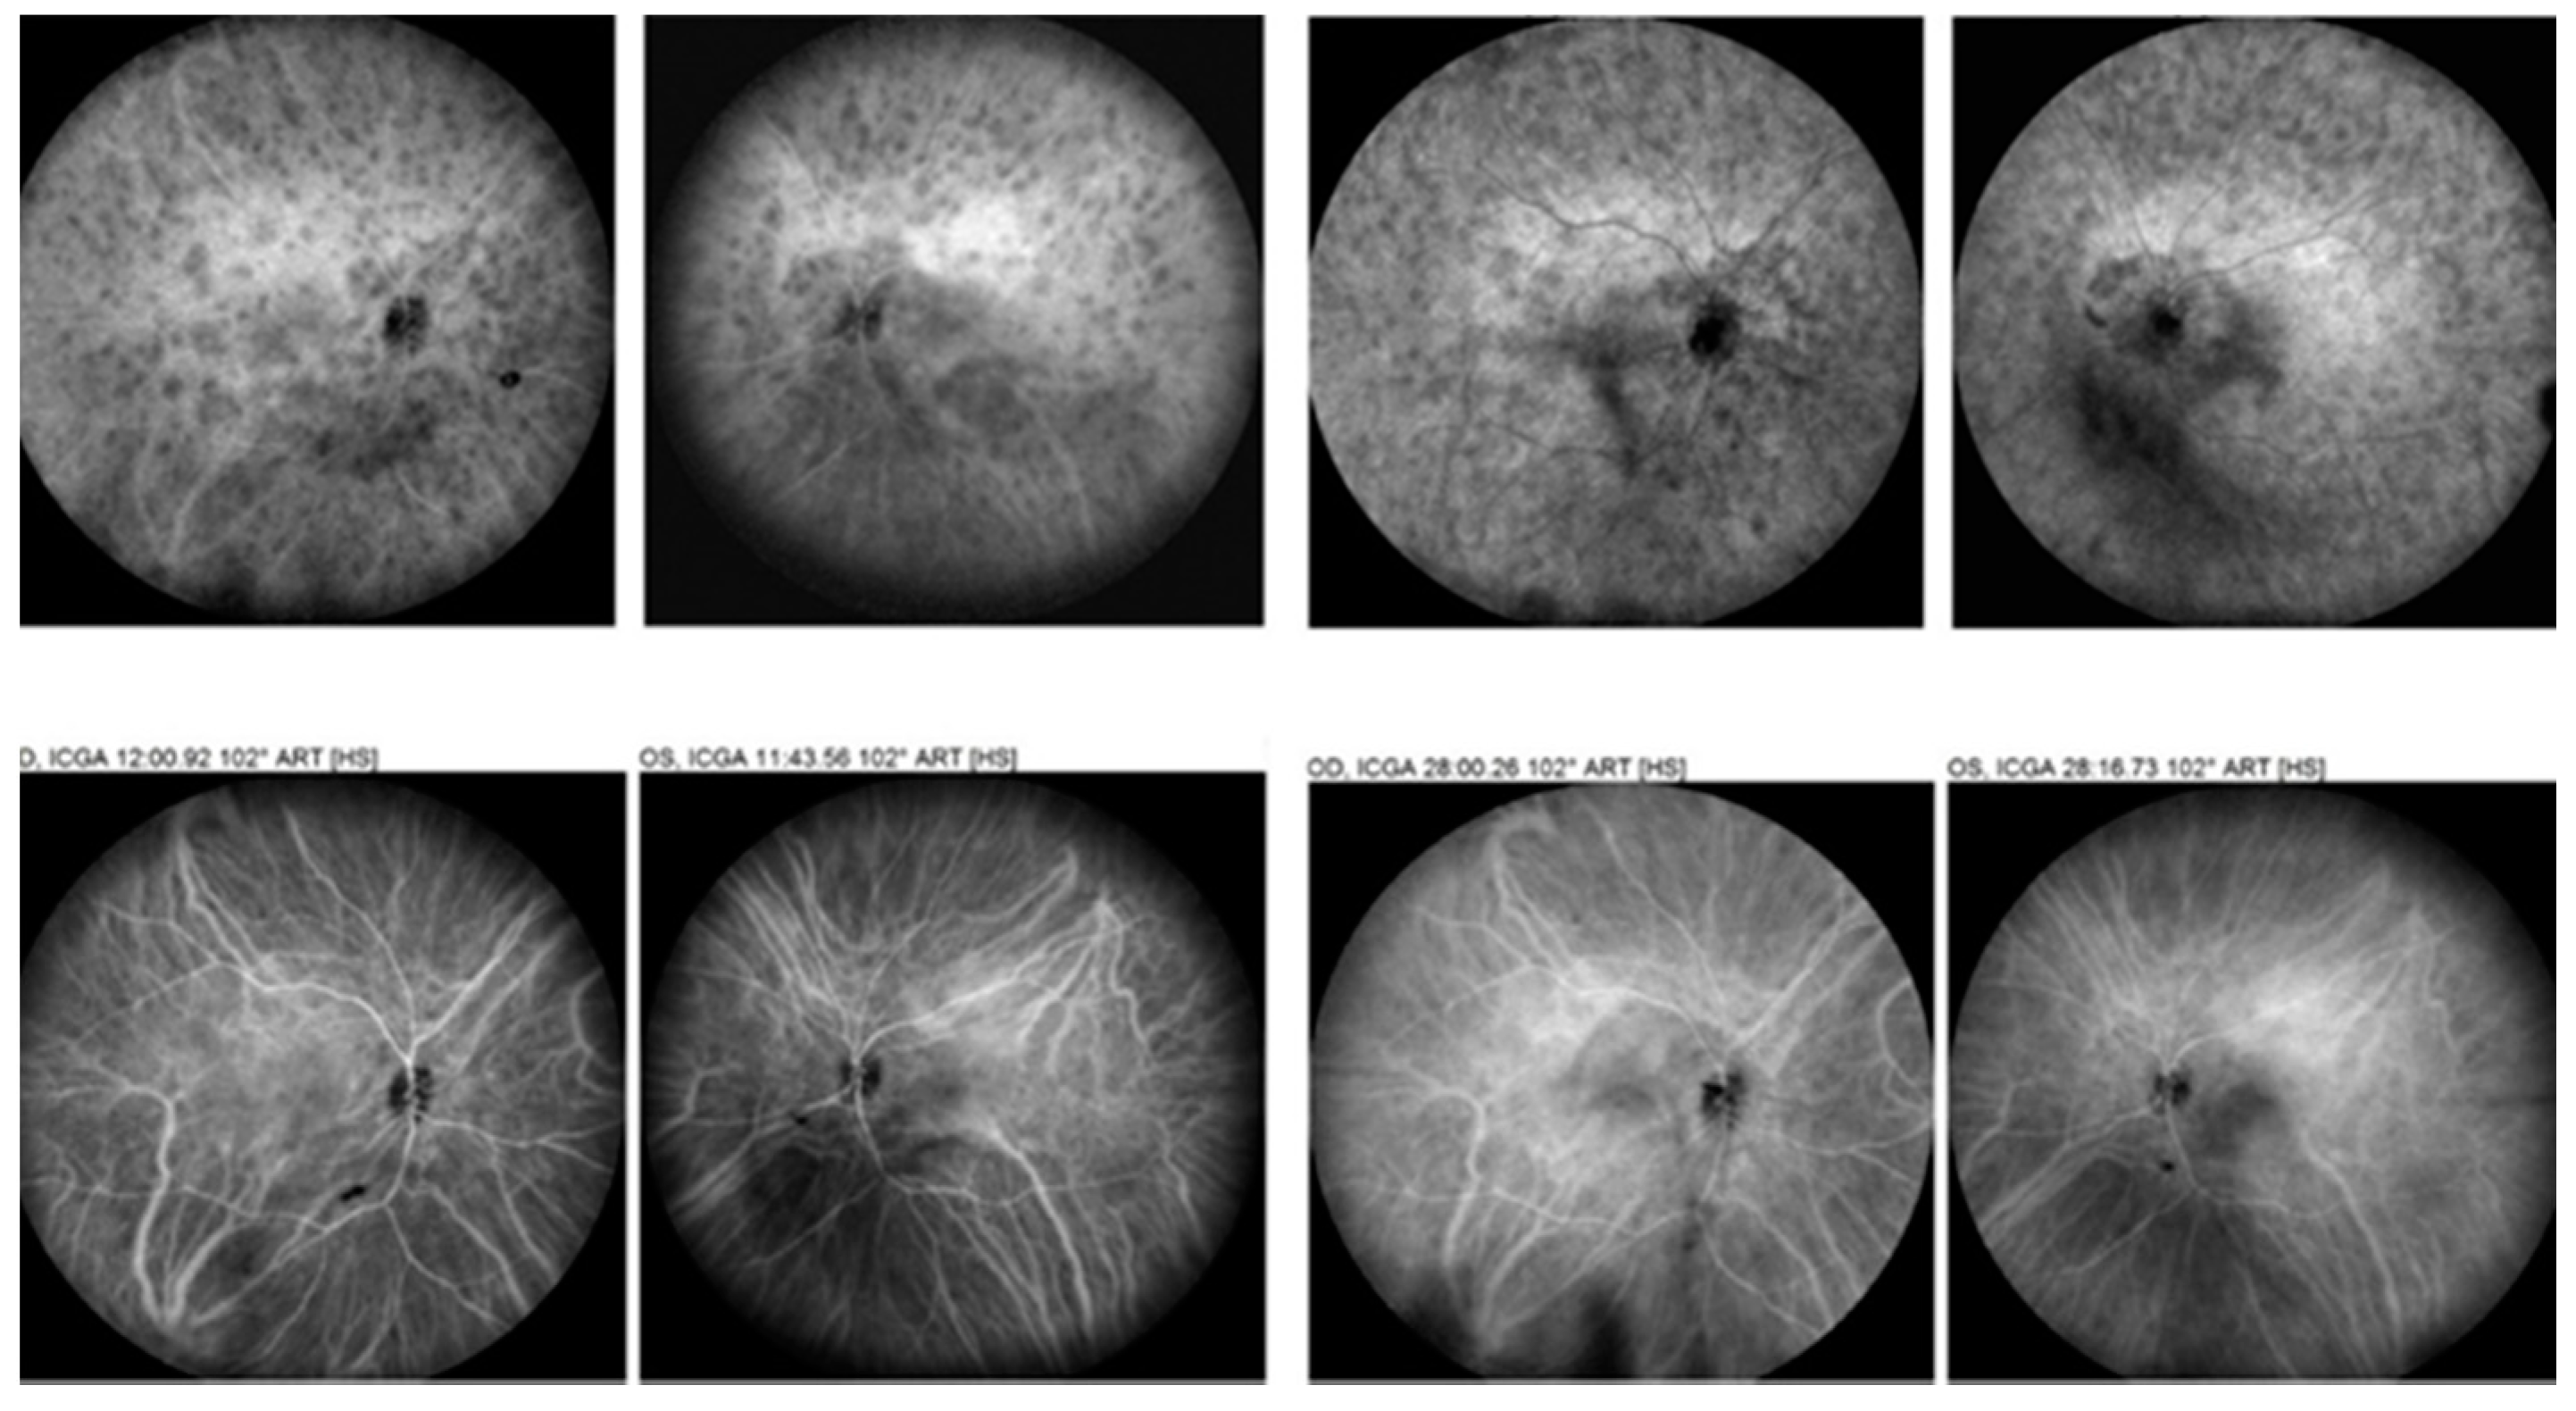

- El Ameen, A.; Herbort, C.P. serpiginous choroiditis imaged by optical coherence tomography angiography. Retin. Cases Brief Rep. 2018, 12, 279–285. [Google Scholar] [CrossRef]

- Balci, O.; Gasc, A.; Jeannin, B.; Herbort, C.P., Jr. Enhanced depth imaging is less suited than indocyanine green angiography for close monitoring of primary stromal choroiditis: A pilot report. Int. Ophthalmol. 2017, 37, 737–748. [Google Scholar] [CrossRef]